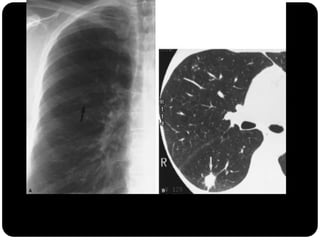

Padrão de árvore em brotamento:Acúmulo de

secreções em pequenas vias aéreas ocorrendo

principalmente em infecções